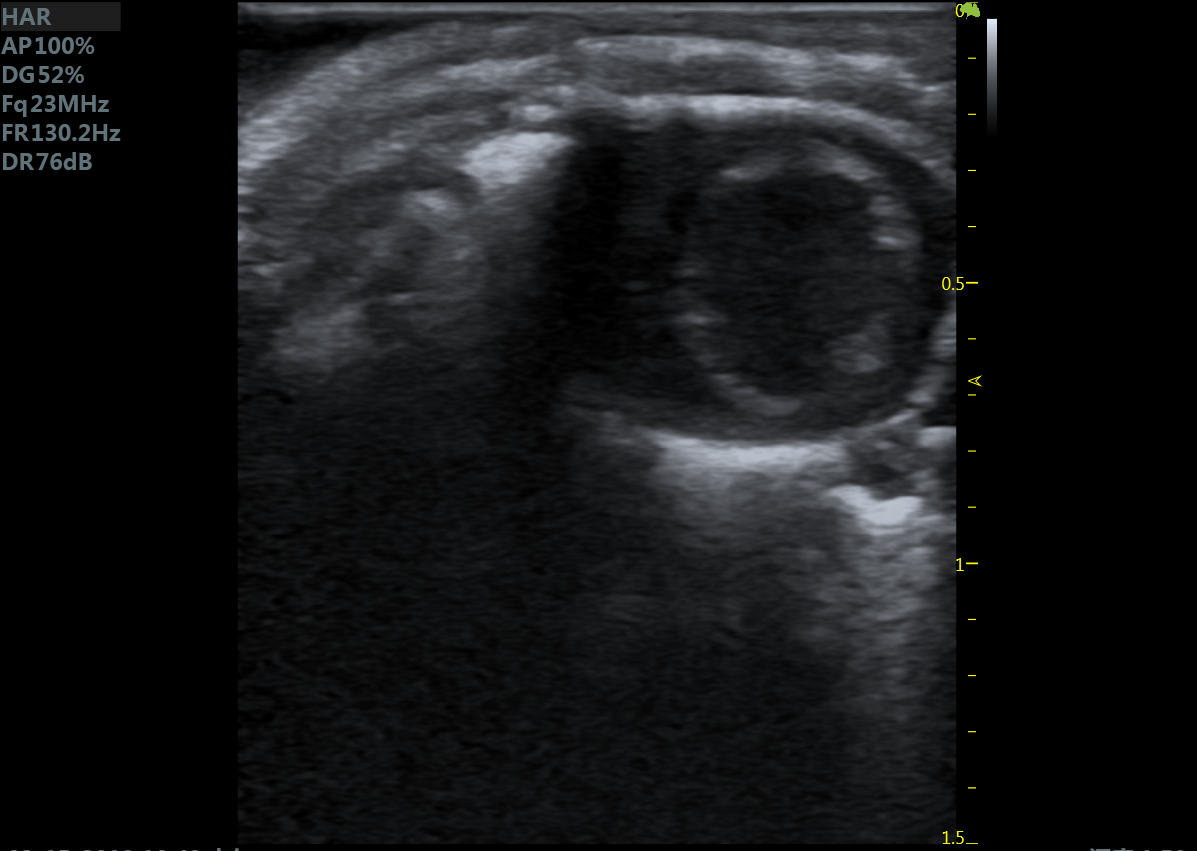

23MHz高频探头,优秀卓越的浅表显影

小鼠长轴B型 小鼠短轴B型

小鼠乳头肌水平 小鼠肝脏